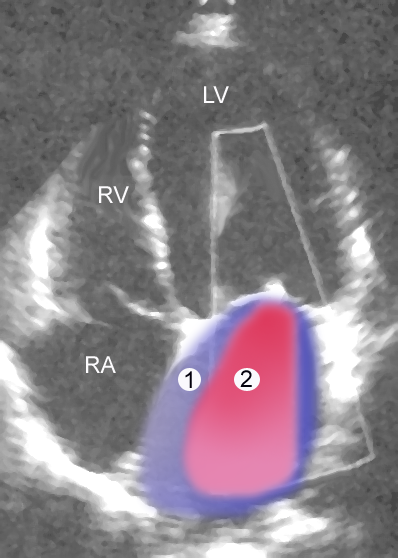

심장 초음파 검사는 승모판 역류(MR)의 진단을 확인하는 데 일반적으로 사용된다.[16] 경흉부 심장 초음파(TTE)에서 컬러 도플러 혈류 검사는 심실 수축기 동안 좌심실에서 좌심방으로 혈액의 제트가 흐르는 것을 보여준다. 또한 확장된 좌심방과 심실, 그리고 감소된 좌심실 기능을 감지할 수 있다.[11] 필요한 경우, 심장의 뒤쪽도 볼 수 있으므로 경식도 심장 초음파 검사(TEE)로 더 선명한 영상을 얻을 수 있다.[17]